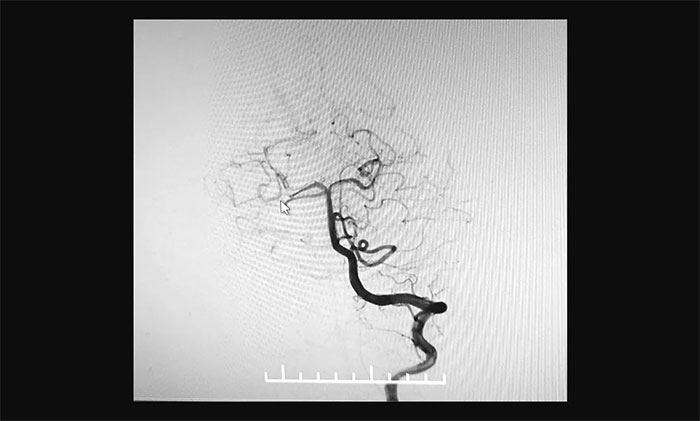

最终,在麻醉科团队及导管室介入团队的密切配合和监护下,神经外科于耀宇主任团队历时2小时,为王女士顺利实施脑血管造影+颅内动脉瘤栓塞术。术中,DSA造影确诊右侧小脑上动脉夹层动脉瘤,动脉瘤瘤体大小约为4x3 mm。术中,于耀宇主任凭借娴熟的技术,克服血管迂曲等困难,将栓塞导管成功送入夹层动脉瘤内,最终顺利栓塞夹层动脉瘤。术后,再次造影未见动脉瘤显影,见远端分支显影良好,“炸弹”危险被成功解除。术后,患者顺利苏醒,无神经功能障碍。

▲ 栓塞前